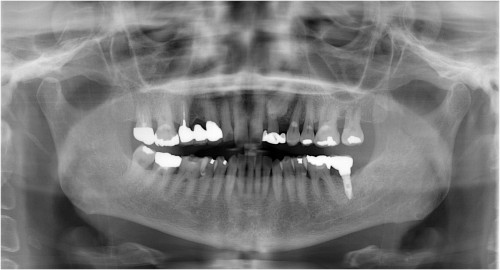

術前パノラマ写真